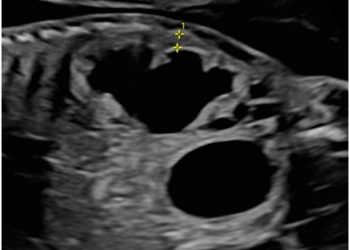

Cari colleghi, vi presentiamo la guida al counseling di Luglio sui leiomiomi uterini Potrete scaricarla cliccando sul link. Grazie a...

Cari soci, questo mese un nuovo video "How to do", dedicato alla terminologia e classificazione MUSA Grazie a Francesca Arezzo!...